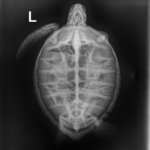

4.7 lbs. non-FP juvenile green

Missing right front flipper and a chunk out of left rear flipper (old injuries) minor abrasions and bruising on carapace and plastron.